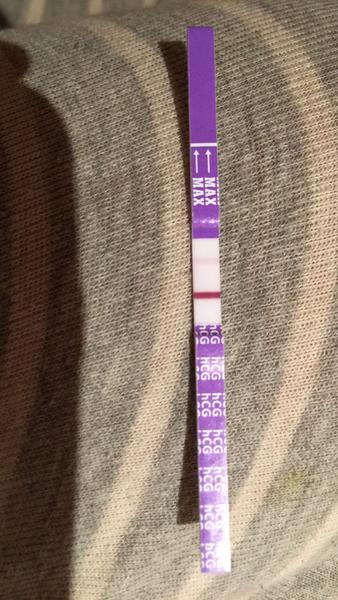

Duch na teste

ahojte babule, mam taku otazku...mate skusenost ze pocas 3 dni vam nesilnela druha ciarka na teste ale bola rovnaka???ako duch????